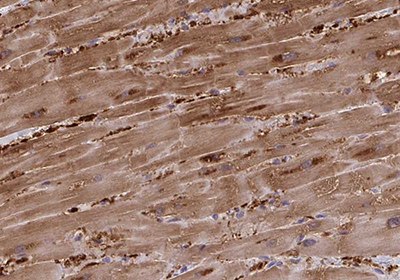

A myocyte is the functional cell type of muscle tissue. There are three different types of myocytes with distinct properties and include smooth, cardiac and skeletal muscle cells. Smooth muscle cells (SMC) build up as involuntarily controlled, non-striated muscles in the walls of visceral tissues and blood vessels. The master regulation of smooth muscle gene expression is mediated by myocardin. Cardiomyocytes, or heart muscle cells, are involuntarily controlled, striated cells confined to the heart. Cardiomyocytes are, among other factors, regulated by GATA4 and myocardin. Skeletal muscle cells are striated muscle cells under voluntary control and are attached to the skeleton by tendons. MyoD1 is a key regulator of skeletal (striatal) muscle cell differentiation. Figures 5A-C show immunostainings exemplifying specific antibody markers for each type of muscle cell.

Figure 5B.Immunohistochemical staining of cardiac muscle cell showing high expression of Fatty Acid Binding Protein 3 in human heart muscle using Anti-FABP3 polyclonal antibody (HPA055754).